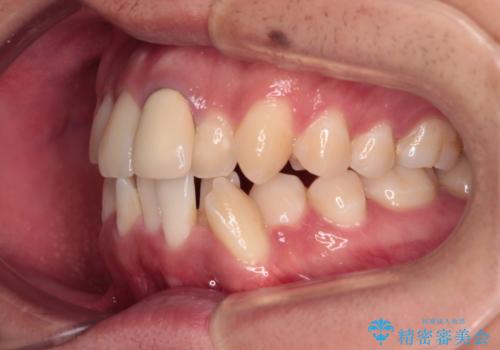

- 前歯のデコボコや八重歯を気にして来院された患者様です。

他院でワイヤー矯正を行うつもりでいらっしゃったそうですが、通院が難しくなったとのことで当院での治療を希望されて来院されました。

上下ともに歯列幅が狭く、その影響でデコボコになっていたため、ワイヤー装置を用いて歯列を側方に拡大しながら、デコボコを解消していくこととしました。